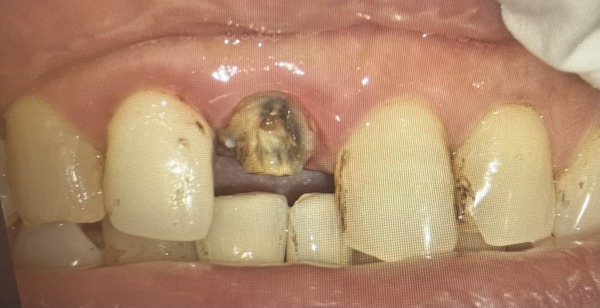

エックス線写真によると、前歯2本は神経を取り除いており、土台に「金属」を使用した差し歯であることが分かりました。被せ物と歯の間に隙間ができており、治療前の写真では歯が部分的に黒く変色しています。

この黒色化には2つの理由があります。

1.神経を取り除いたため:

歯髄(しずい)は歯に水分や栄養を与えている組織です。歯髄を取り除くことで歯は乾燥し、くすんだ色になります。

2.詰めた材料の影響:

歯の内部に使用した「金属」が、歯の色に影響を与えます。

よく見ると、2本とも根尖部のエックス線透過像はありませんが、細菌感染していることが考えられるので、根管治療から始めていくことにしました。

被せ物を外すと虫歯になっていました。患者様は、被せ物が揺れていることも虫歯があることも自覚されておらず、驚いた様子でしたが、差し歯が突然外れる前に治療を始めることができて良かったとおっしゃっていました。